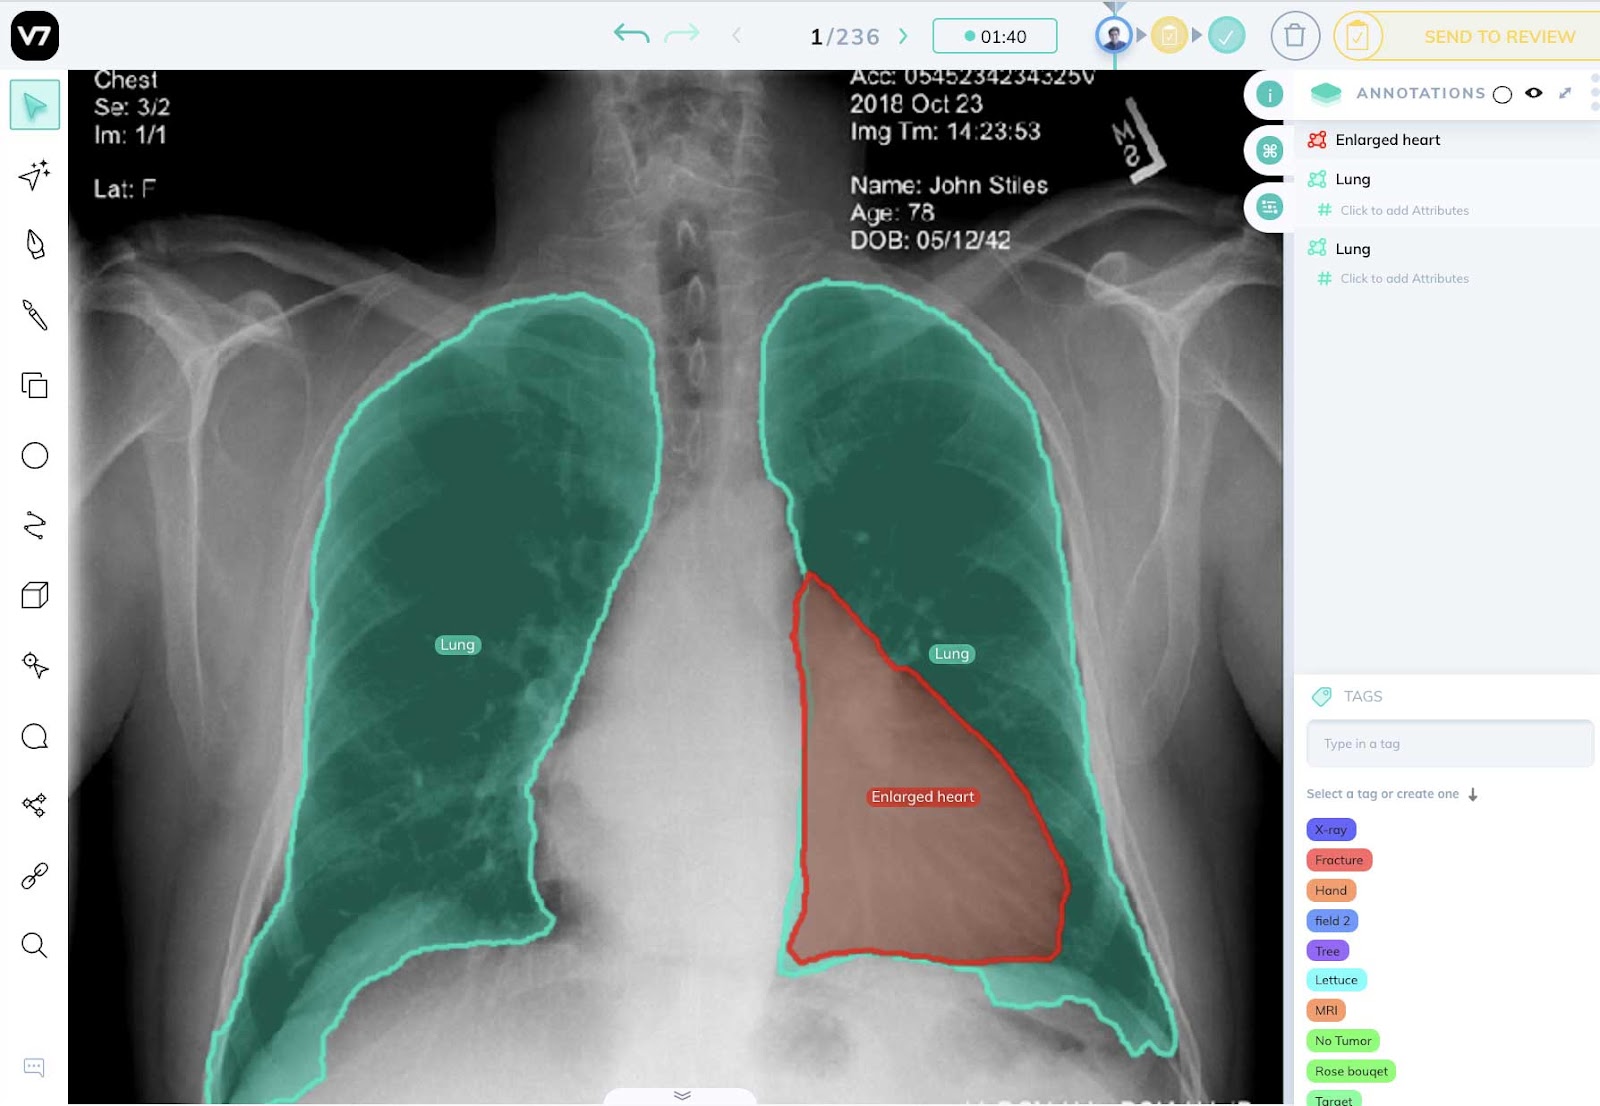

X 射线分析

在医学 X 射线成像的背景下,计算机视觉可以成功地应用于治疗和研究、MRI 重建或手术计划。

尽管大多数医生仍然依靠手动分析 X 射线图像来诊断和治疗疾病,但计算机视觉可以使该过程自动化,从而提高效率和准确性。

最先进的图像识别算法可以在 X 射线图像中识别出人眼无法察觉的模式。

CT和核磁共振

计算机视觉也广泛应用于 CT 扫描和 MRI 的分析。

从设计人工智能系统到分析放射图像的准确度与人类医生相同(同时减少疾病检测时间),再到提高 MRI 图像分辨率的深度学习算法——计算机视觉是改善患者预后的关键。

使用计算机视觉分析 CT 和 MRI 扫描可以帮助医生检测肿瘤、内出血、血管堵塞和其他危及生命的疾病。该过程的自动化也被证明可以提高准确性,因为机器现在可以识别人眼看不到的细节。